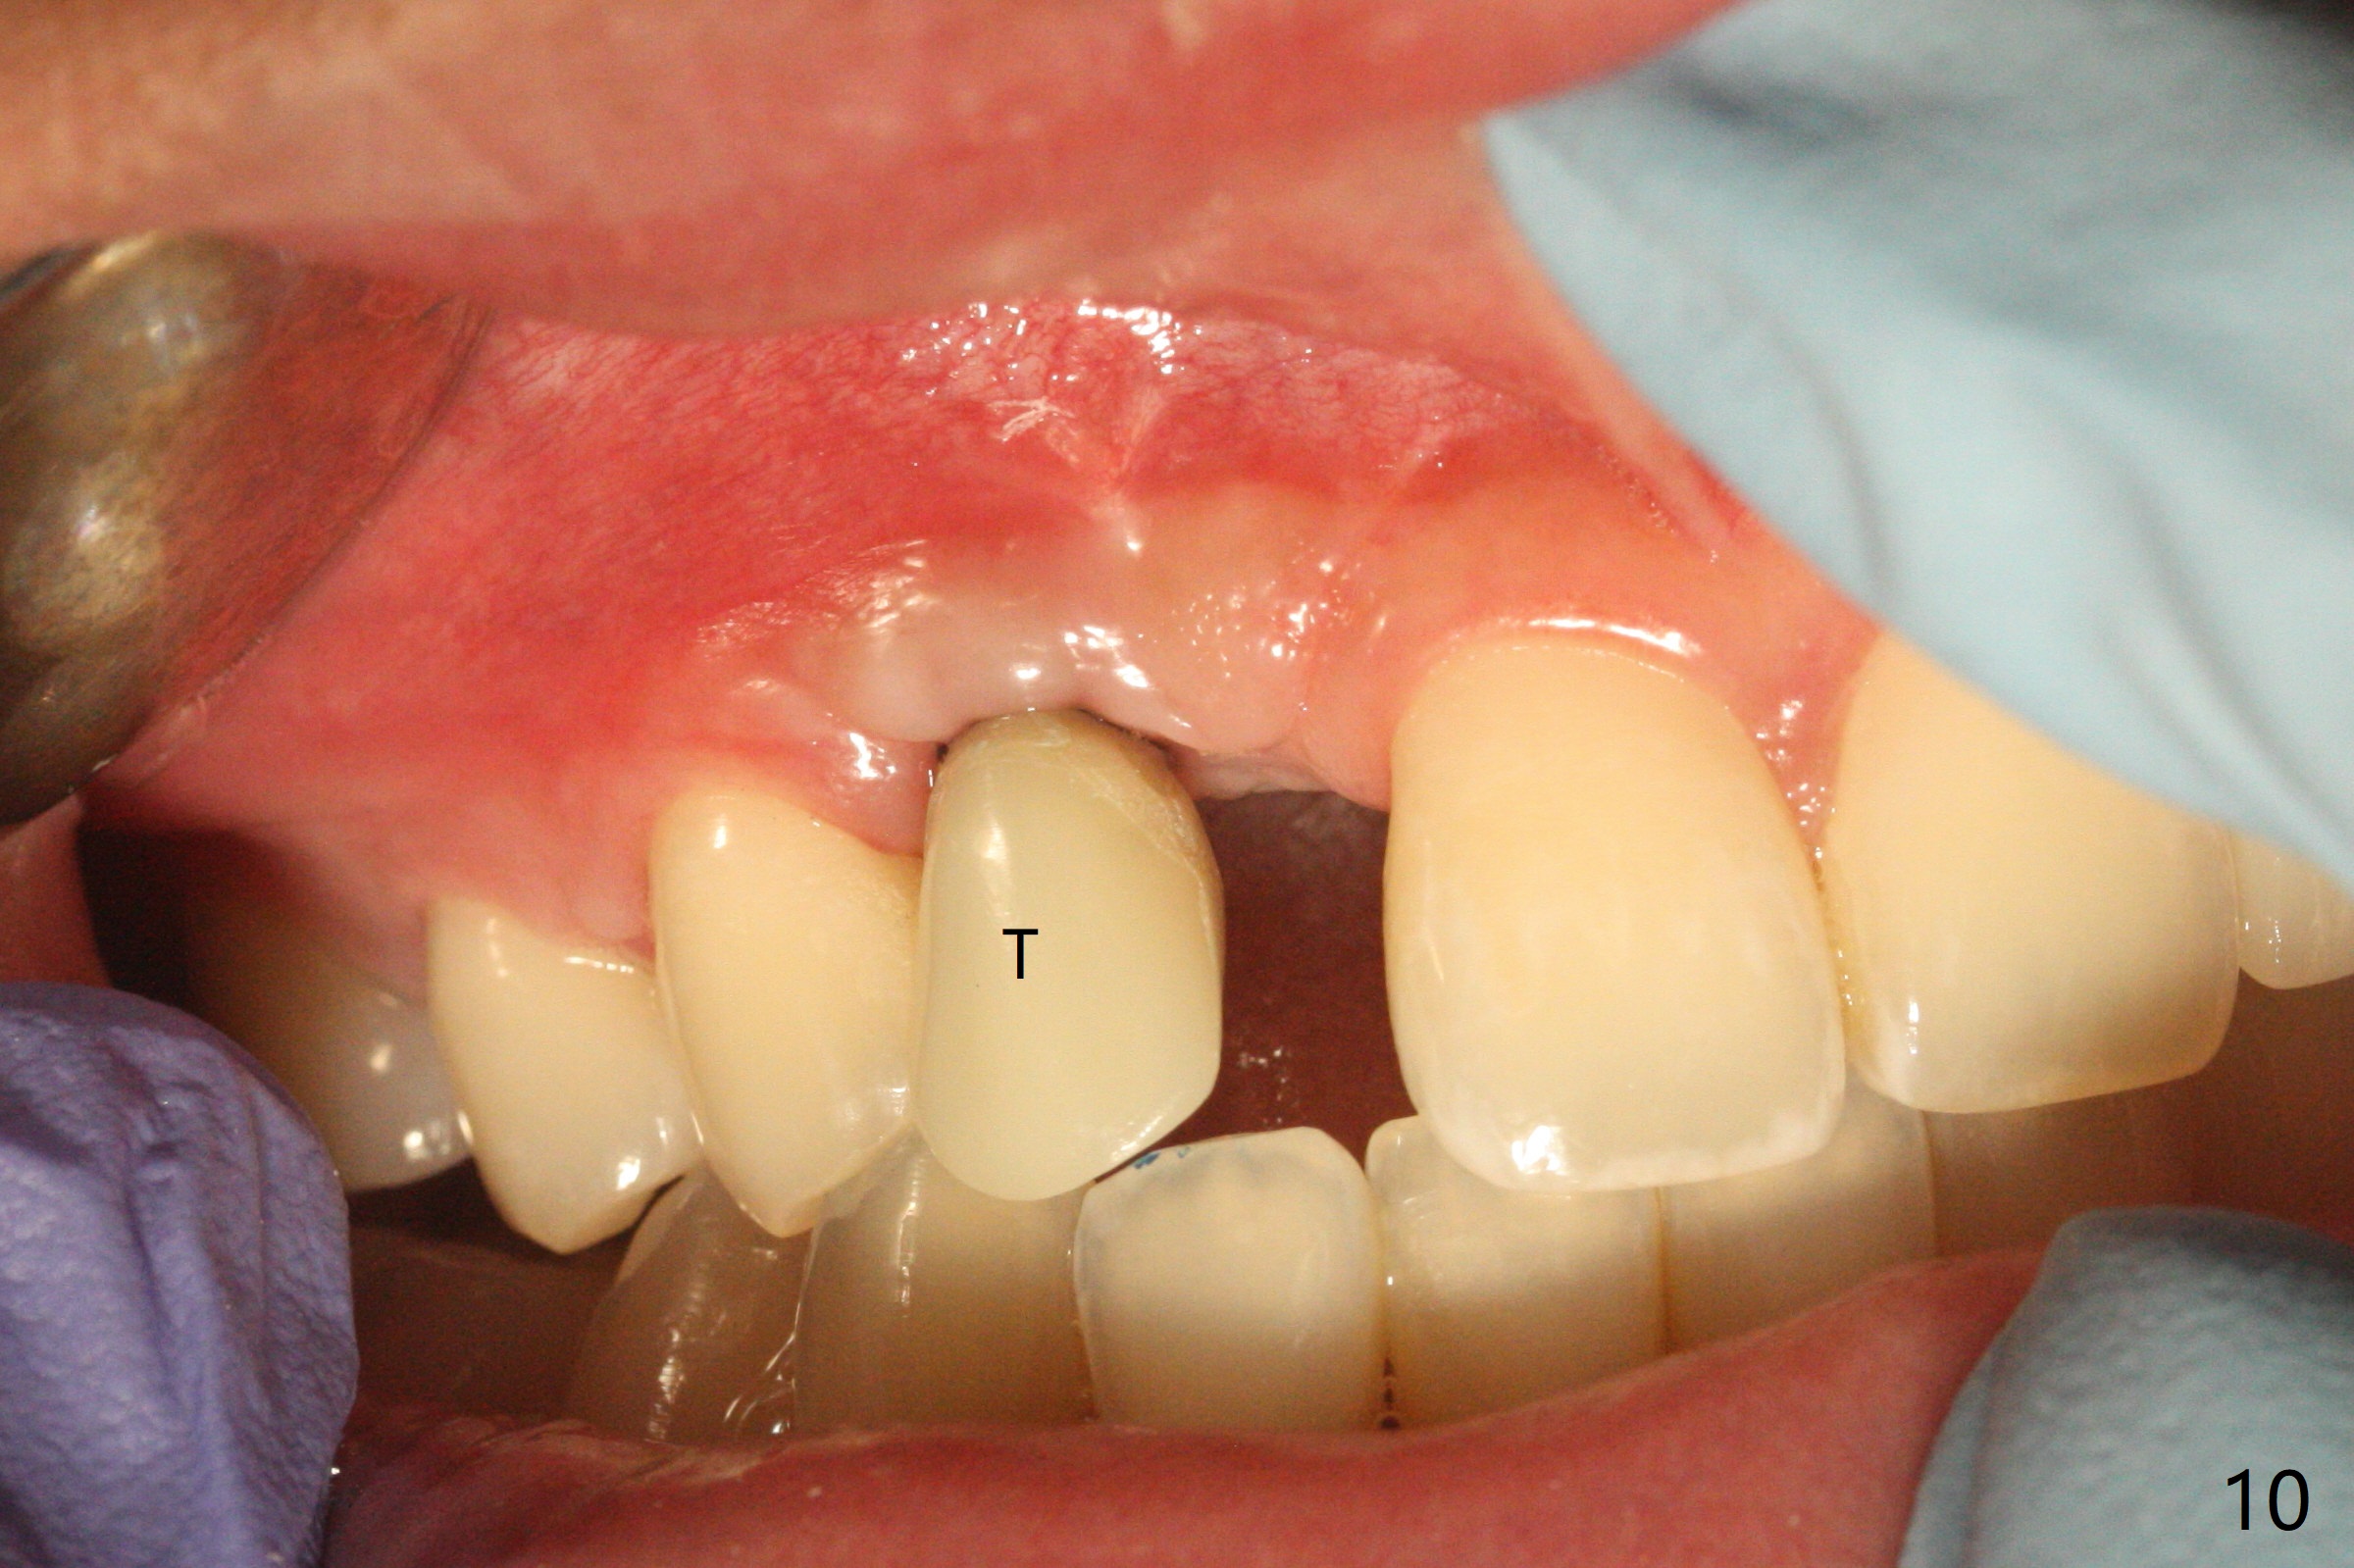

右上尖牙植体拔除,植骨后6个月,切开显示不可吸收膜覆盖的牙槽骨尚饱满(图一),不可吸收膜下面形成一个膜(可能是骨膜,图二:M),在导板指导下,植入3x12(2)毫米一段式植体,颊侧(图三),腭侧(图四)骨下,稍微穿过窦底(图五),植体覆盖粘性骨粉(图六)和PRF膜后,4-0 PGA缝合。伤口有一定张力,使用牙周敷料。术后10天没有疼痛(就没有骨坏死),由于基台存在,牙周敷料没有脱落迹象(图七),也没有撤除。敷料术后13天脱落,伤口好像正常愈合(图八)。由于病人即将回外州上学,提前取模。他喜欢左边牙冠修复形式(牙冠覆盖牙龈),而我们想让牙冠位于牙龈舌侧(图十:T(临时牙冠))。